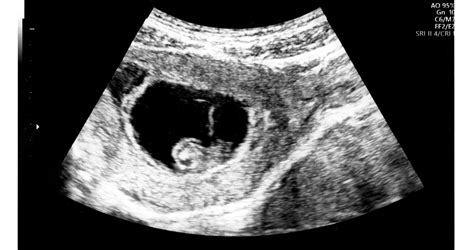

A halvaszületések okainak feltárása kulcsfontosságú lehet a jövőbeli terhességek szempontjából. Az orvosok a halvaszületéseket három típusba sorolják: korai (20-27. hét), késői (28-36. hét) és terminus (37. hét utáni) halvaszületés. A kivizsgálás során számos vizsgálat jön szóba, mint például az ultrahang, a magzatvíz vizsgálata (amnioszkópia), a lepény és a magzat boncolása, valamint genetikai vizsgálatok.

A köldökzsinór problémái, mint például a nyakra tekeredés, a terhességek 6-29%-ában fordulnak elő. Bár az esetek 80%-ában ez tünetmentes, a zsinór megfeszülése megzavarhatja a magzat oxigénellátását, ami halvaszületéshez vezethet. A 36-37. heti ultrahangvizsgálat és a Doppler-vizsgálat segíthet ezeknek a problémáknak az időbeni felismerésében. A perinatális boncolás is fontos információkkal szolgálhat, és segíthet az ismétlődés kockázatának felmérésében.

- Ultrahangvizsgálat: Segít a magzat szívverésének ellenőrzésében és a fejlődési rendellenességek felismerésében.